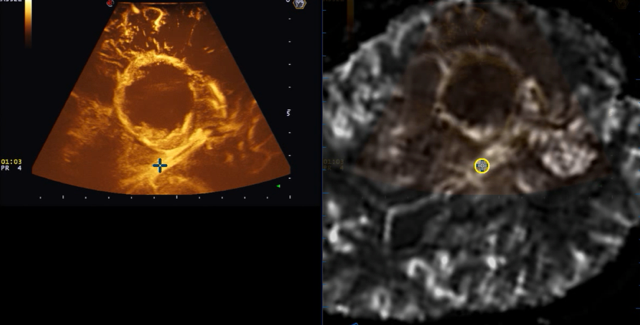

To test this idea, the researchers compared preoperative DSC MRI data with intraoperative CEUS data, both obtained from 31 patients undergoing brain tumor surgery. Fusion imaging was employed for real-time neuronavigation during the surgical procedures, enabling precise alignment and guidance.

The results revealed that the MRI perfusion patterns correlated both qualitatively and quantitatively with intraoperative CEUS, suggesting that DSC MRI can serve as a noninvasive biomarker to predict microbubble distribution. Importantly, the CEUS images also allowed the team to quantitatively discriminate between tumoral and normal brain tissues.